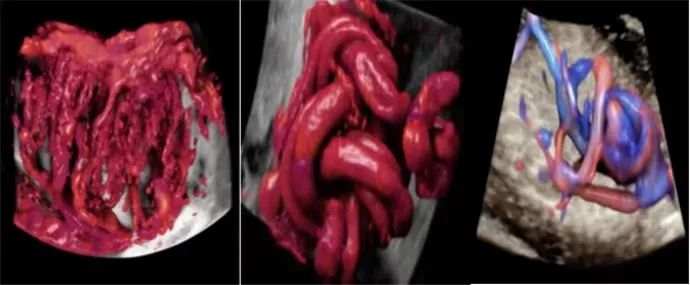

“煊流技术”可真实呈现脐带、胎盘血流,对于深部小血管的立体结构显示极具优势,在评估血管分布或灌注状态时,如同采用血管造影模式。提升产前检查的诊断质量和效率。

盆底三维四维超声有着多平面成像的优势,通过容积数据采集获得更清晰的图像,为临床诊断提供更丰富、有效的信息;妇科肿瘤方面,“煊流技术”提高了微小血管的敏感性,有助于肿瘤良恶性的鉴别诊断。